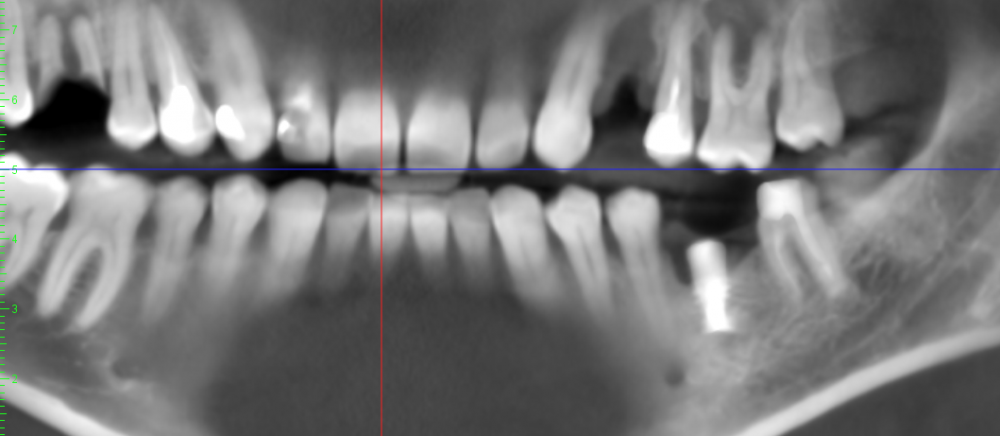

Папа Карло Опубликовано 13 июля, 2021 Поделиться Опубликовано 13 июля, 2021 Здравствуйте. Предлагают удалить зуб 2.6, причина воспаление на корне, проникающее в гайморову пазуху. Зуб не беспокоит вообще, не леченый (с соседними 2.4-2.5 были проблемы). Что можно сделать кроме удаления? Ссылка на комментарий

Bier Опубликовано 13 июля, 2021 Поделиться Опубликовано 13 июля, 2021 можно полечить эндодонтически. а имплантат внизу - удалять Ссылка на комментарий

St. Опубликовано 5 августа, 2021 Поделиться Опубликовано 5 августа, 2021 26 нормальный перспективный зуб, лечите. + соседний 25 нуждается в перелечивании каналов Ссылка на комментарий